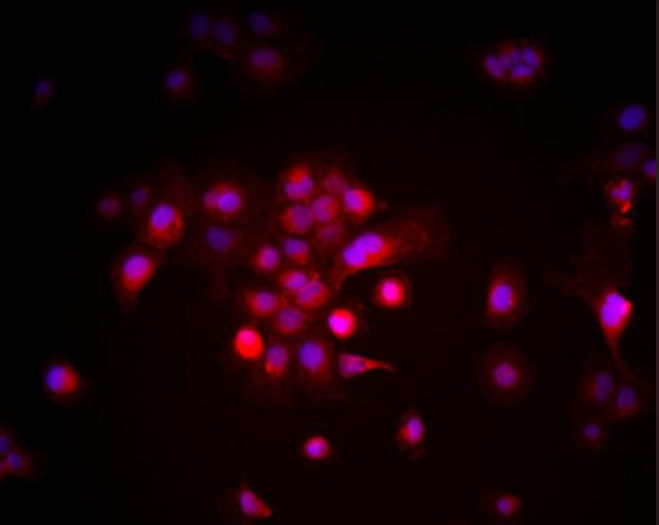

人红白细胞白血病细胞HEL(HEL细胞)来源于人红白细胞白血病组织,是一种用于白血病研究的细胞系。该细胞系具有典型的白血病特征,广泛应用于白血病的生物学研究、药物筛选及治疗策略研究。HEL细胞用于研究白血病细胞的增殖、转移、免疫逃逸及细胞因子分泌等生物学特性。

人红白细胞白血病细胞HEL(HEL细胞)广泛应用于白血病的增殖、转移、免疫逃逸机制等研究。HEL细胞成为研究白血病转移、免疫逃逸及新药筛选的重要工具。研究人员利用该细胞系探讨了肿瘤的转移机制、细胞因子分泌、肿瘤微环境及其与免疫系统的相互作用,为白血病的治疗提供了关键数据支持。